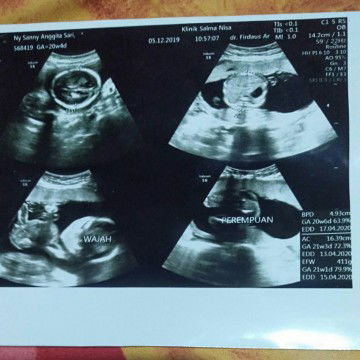

foto usg

Halo bun,aqu mohon info nya ,ini hasil usg aqu kemaren katanya perempuan emang bener fotonya seperti ini?

foto hasil usg4d

Emang iya bun itu kata dokternya perempuan, tapi pas ter akhir usg4dnya ...,kata dokternya" ko ada gununganya,tapi ga keliatan monasnya,ini kaya mis v nya ada"gitu kata dokternya ,jadi nyimpulinnya cowok dulu bun,karna ada gununganya,aku juga jadi bingung bun,mungkin ada bunda2 yg lebih paham dari foto ini.....??